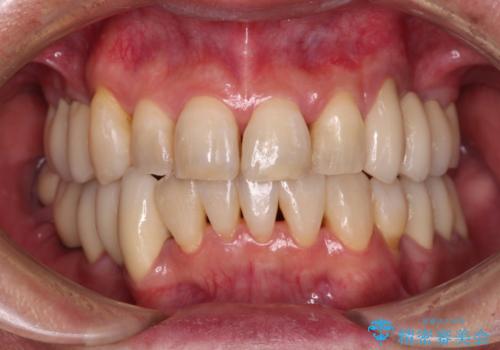

抜歯が必要な左右の奥歯 ブリッジとインプラントによる奥歯の補綴治療